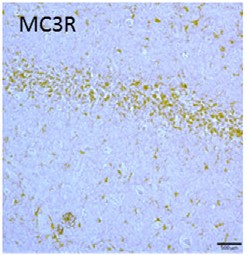

Expression of MC3R in rat hippocampus.Immunohistochemical staining of rat brain sections using Anti-MC3 Receptor (extracellular) Antibody (#AMR-023). MC3R staining (brown) is detected in CA1 region.Adapted from Massey, A.T. et al. (2016) Front. Neurol. 7, 65. with permission of Frontiers.

Massey, A.T. et al. (2016) Front. Neurol. 7, 65.